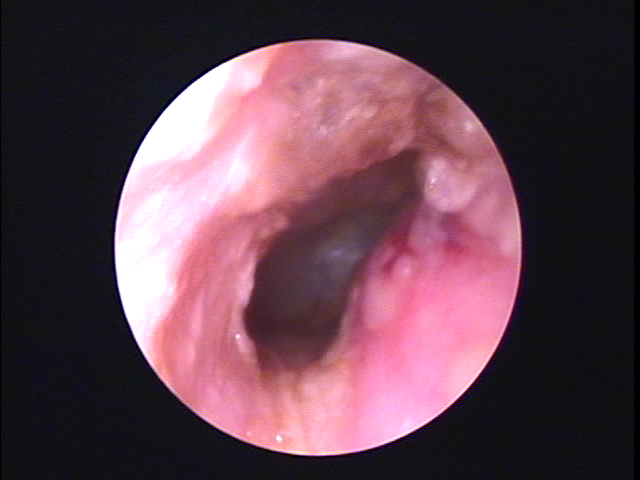

外耳道に炎症が起こって、痛み・耳だれなどの症状があります。